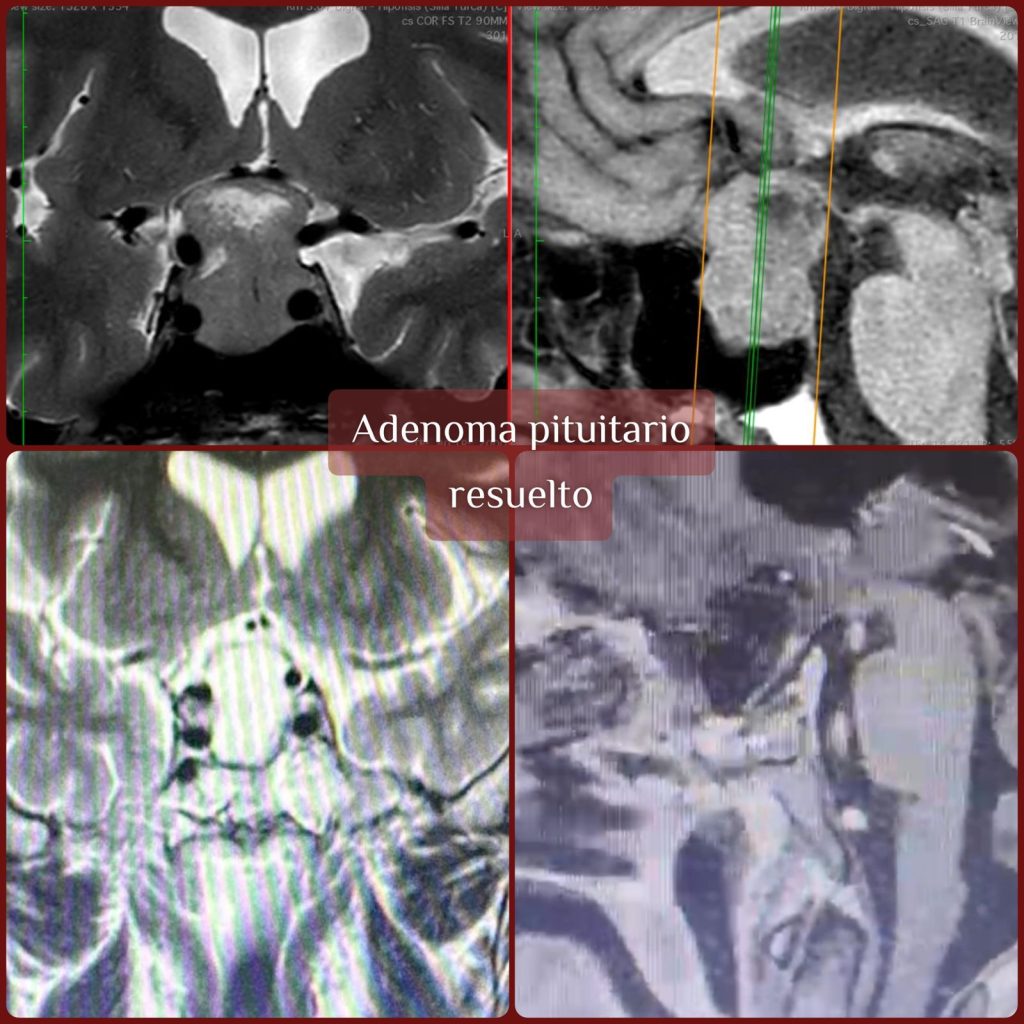

La detección de un adenoma hipofisario se realiza mediante estudios de imagen, principalmente resonancia magnética cerebral, junto con pruebas hormonales específicas. El diagnóstico y tratamiento óptimos requieren la colaboración estrecha entre neurocirugía y endocrinología, ya que el endocrinólogo es clave para interpretar los perfiles hormonales, ajustar tratamientos médicos y dar seguimiento después de la cirugía para asegurar la estabilidad endocrina.

Cirugía endoscópica endonasal: tratamiento moderno y seguro

El tratamiento de elección para la mayoría de los adenomas que causan síntomas es la cirugía endoscópica endonasal, un procedimiento mínimamente invasivo que permite acceder al tumor a través de la nariz, evitando incisiones externas y sin necesidad de abrir el cráneo.